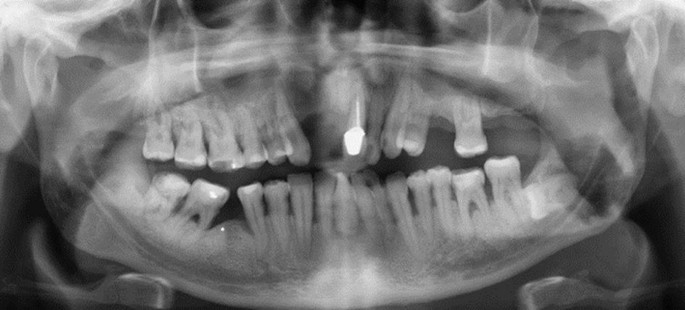

Orthopantomogram of the patient’s dentition

On examination, there was a loss of the nasal columella and saddle nose deformity. Intra-orally, there was complete erosion of the hard and soft palate and destruction of the nasal septum, with superimposed overgrowth of tissue and suppuration extending from the anterior hard palate posteriorly toward the oropharynx. The defect was surrounded with florid angiomatous tissue and bordered with crusted necrotic tissue (Fig. 5, Fig. 6). All remaining maxillary teeth were mobile (Fig. 7).